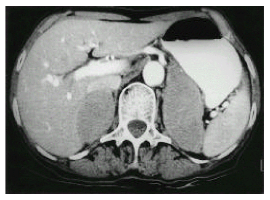

Citation: Shohei SH, Wang M, Zhou YQ, et al. Clinical Image of Metastatic Non-Hodgkin’s Lymphoma Manifesting as Bilateral Adrenal Masses. Clin Image Case Rep J. 2020; 2(2): 114.